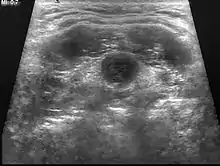

It develops from tissues left over after the formation of the thyroid gland during early development.[1] Diagnosis is usually by ultrasound.[1] Other conditions that can present similarly include lymphadenopathy, dermoid cysts, and second branchial cleft cysts.[1]

| Ultrasound | Image capture of the degree of mass and its surrounding tissues. |